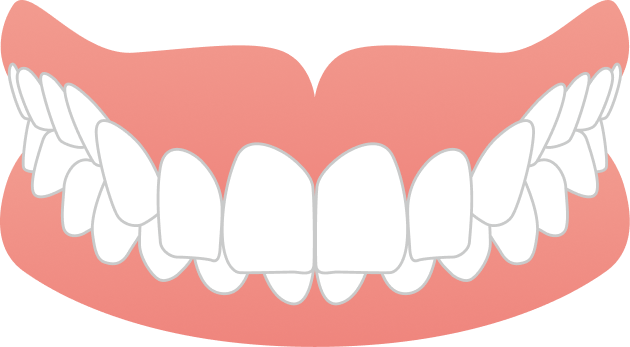

治療は、マウスピース矯正インビザラインにて矯正治療を行い、歯列全体のバランスと噛み合わせを考慮しながら計画を立てました。抜歯を行うことなく治療を進め、治療期間は2年10ヶ月で歯並びが整っています。

自然な見た目を保ちながら、無理なく歯並びを改善することができた症例です。

AFTER

| 施術内容 | 歯全体のマウスピース矯正システム「インビザラインフル」を用いた治療 |

| 治療期間 | 2年10ヶ月 |

| 費用 | 924,000円(税込) |